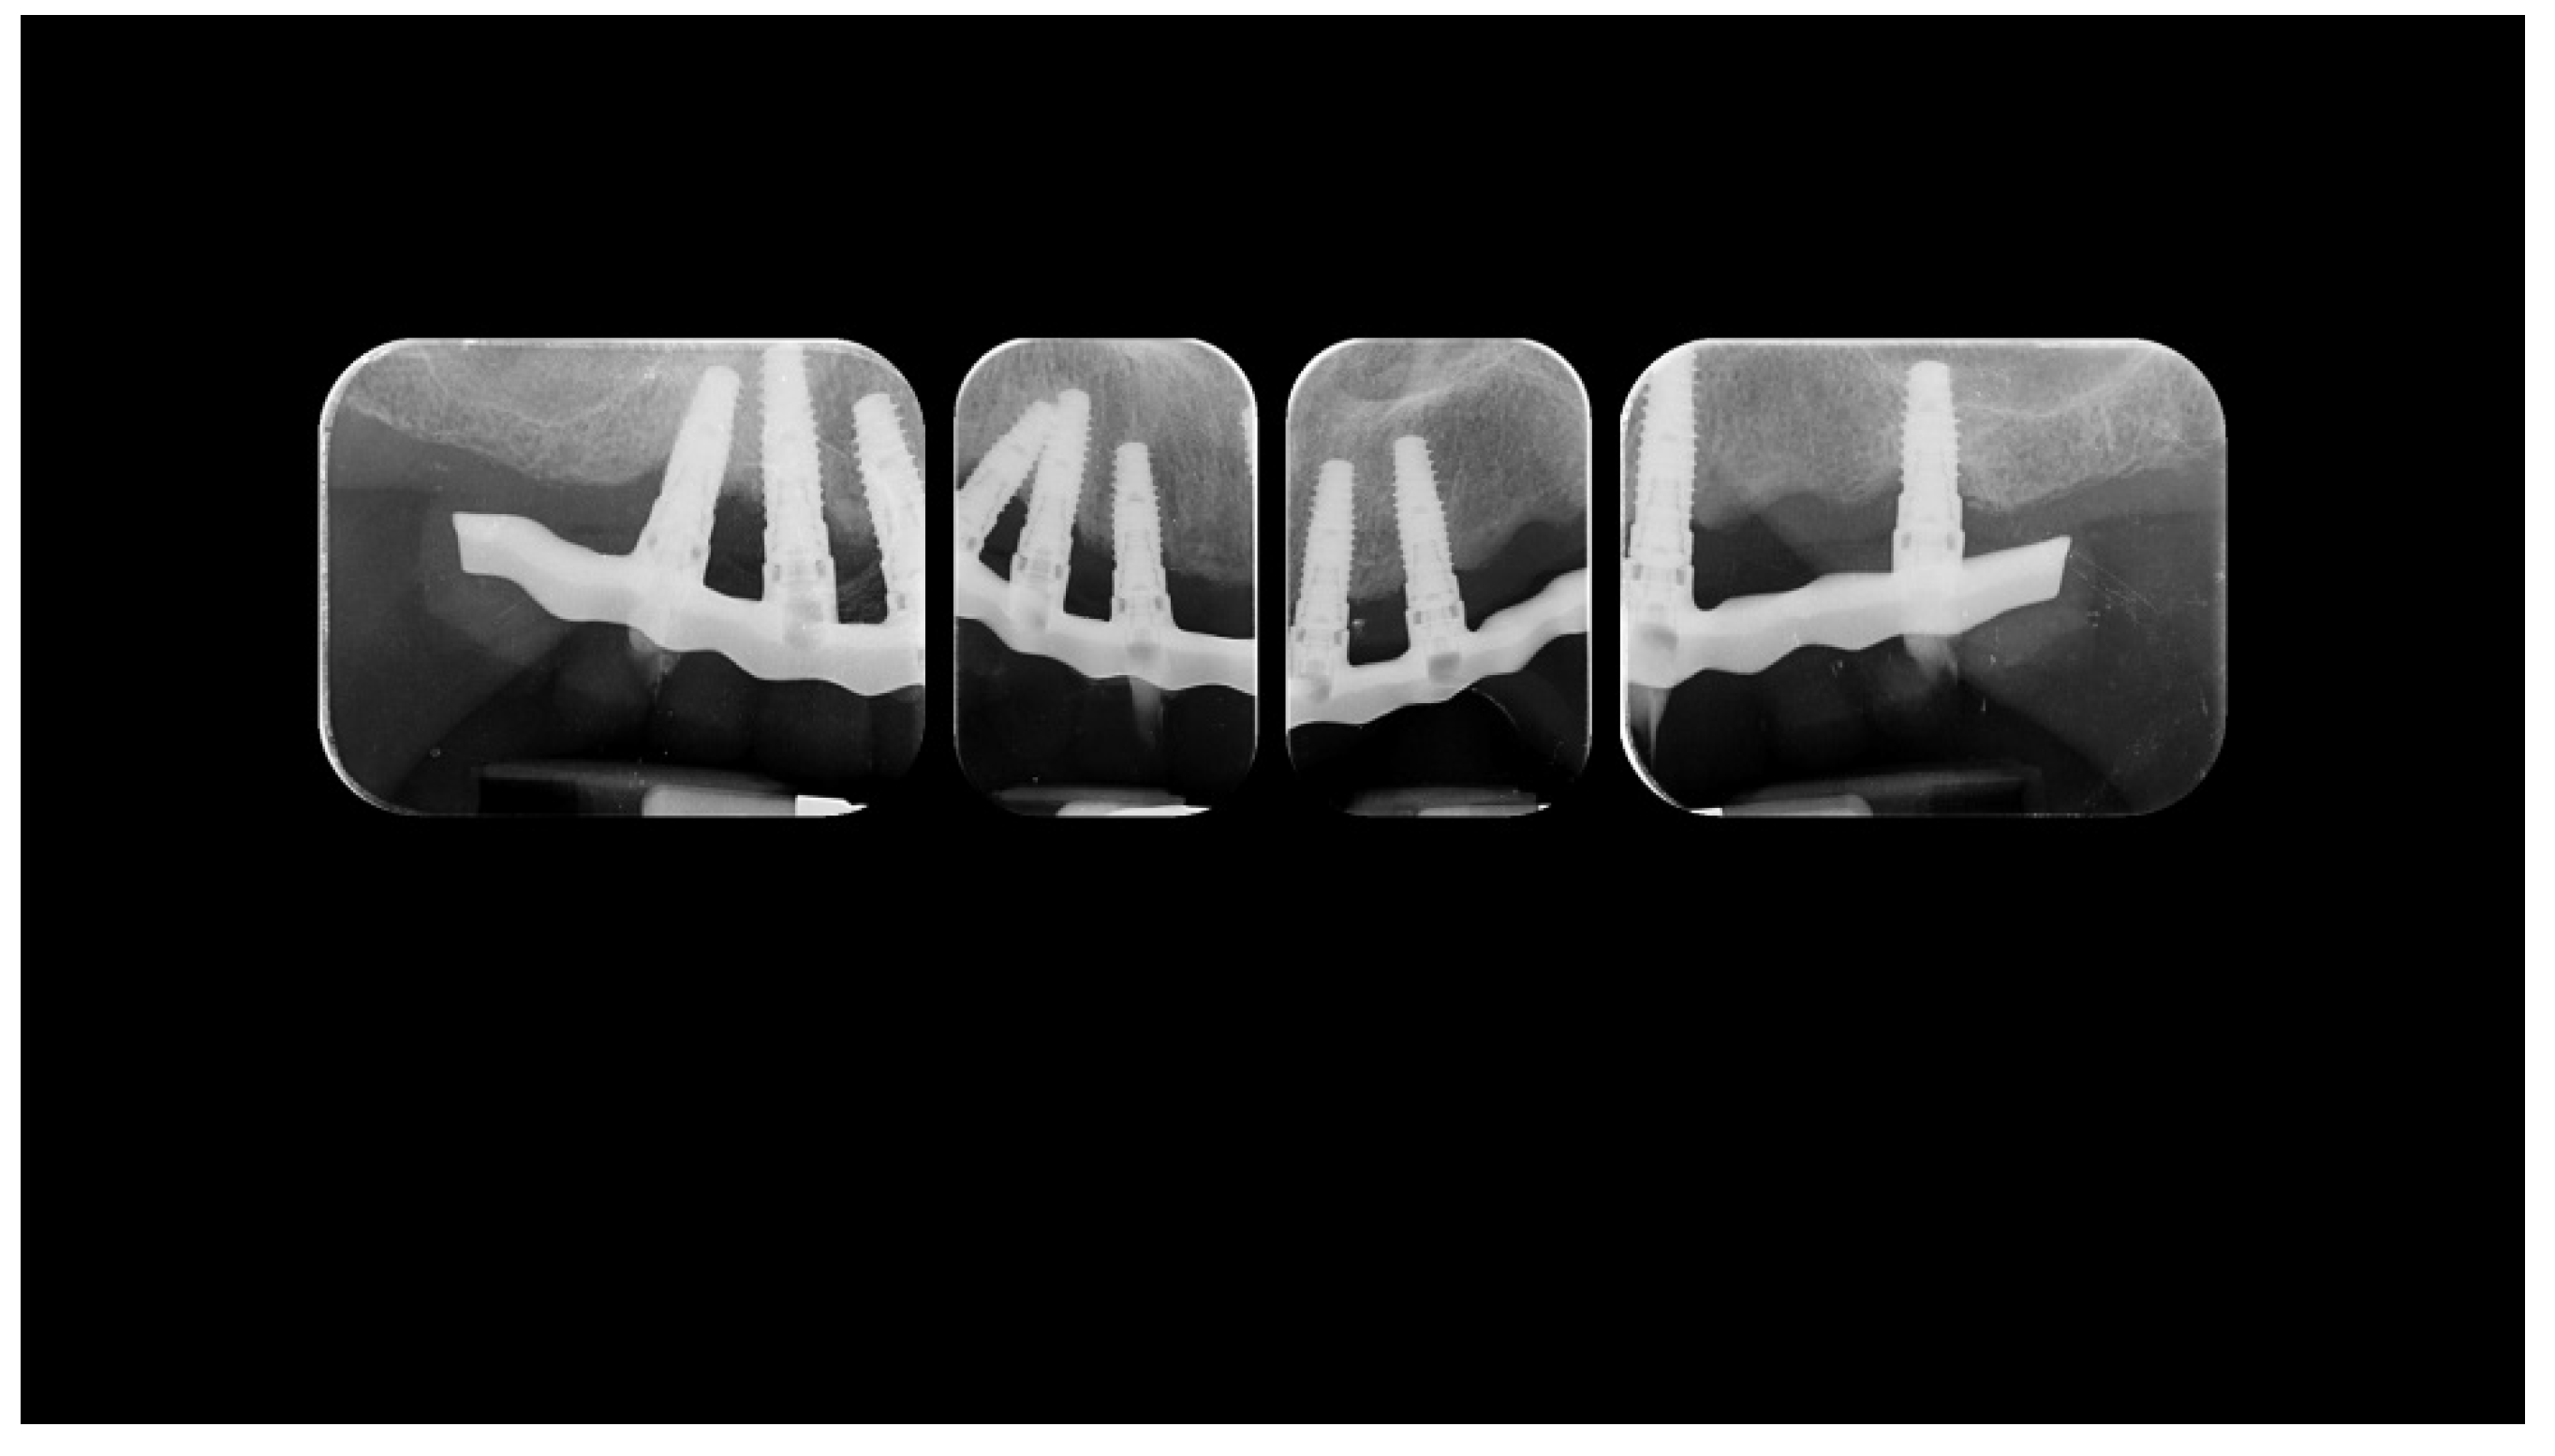

Radiographic status of the new work 1 year after delivery.

3. Discussion